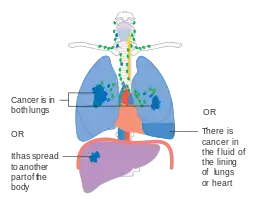

Lung cancer staging is an assessment of the degree of spread of the cancer from its original source.[77] It is one of the factors affecting both the prognosis and the potential treatment of lung cancer.[2][77]

The evaluation of non-small-cell lung carcinoma (NSCLC) staging uses the TNM classification (tumor, node, metastasis). This is based on the size of the primary tumor, lymph node involvement, and distant metastasis.[2]

Using the TNM descriptors, a group is assigned, ranging from occult cancer, through stages 0, IA (one-A), IB, IIA, IIB, IIIA, IIIB, and IV (four). This stage group assists with the choice of treatment and estimation of prognosis.[80]

M1 | IV |

SCLC has traditionally been classified as "limited stage" (confined to one-half of the chest and within the scope of a single tolerable radiotherapy field) or "extensive stage" (more widespread disease).[2] However, the TNM classification and grouping are useful in estimating prognosis.[80]

- Diagrams of main features of staging

- Stage IIIB lung cancer

- Stage IV lung cancer